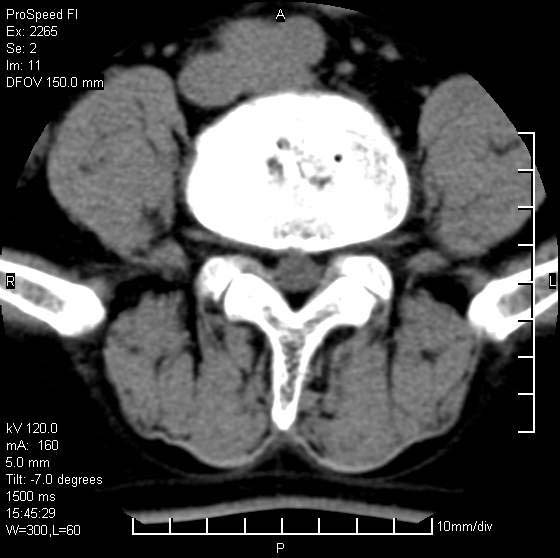

以下是引用qiushi在2007-8-22 17:26:00的发言:[br]没骨窗![br] 1、 l5~s1间盘膨出伴轻度突出(中央型)、变性。[br] 2、l4~5间盘膨出伴突出(右侧远外侧型)。[br] 3、l3~4间盘膨出。[br] 4、腰椎退行性变。[br]

以下是引用随缘的人在2007-8-22 20:56:00的发言:[br]腰椎退行性变:1。l4/5,l5/s1膨出[br] 2。l5/s1间盘退行性变 [br] 3。腰椎骨质增生

以下是引用liaizhi在2007-8-22 22:13:00的发言:[br]1,l4-5锥间盘膨出,2,l5-s1椎间盘膨出并退变(椎间盘呈真空征);3,血管瘤(椎体骨小梁稀疏粗大)?